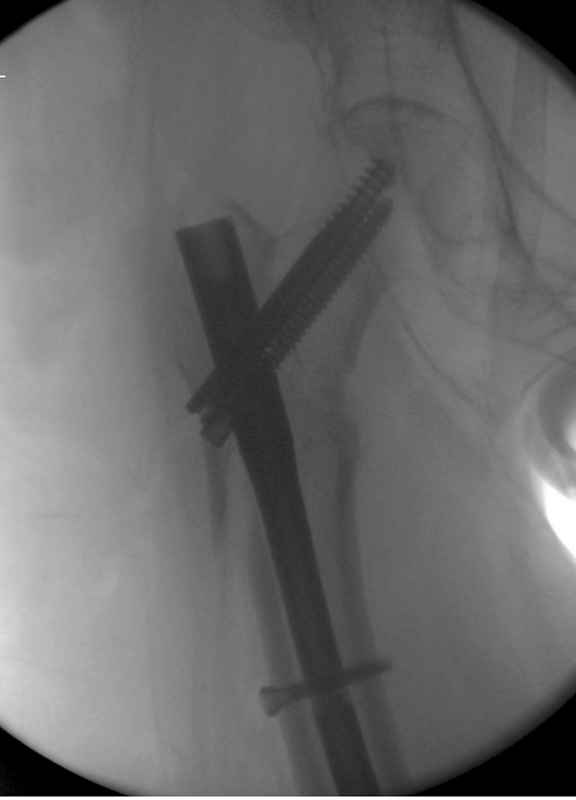

судя по картинкам с ЭОПа явно использовались приемы непрямой репозиции под его контролем, а так же интраоперационный ЭОП-контроль положения винтов, без такого контроля операция может ухудшить ситуацию (опять же учтите сроки) т.к. результат буде зависеть в большей степени от искусства хирурга, а не от технологии

Здесь 83 года, травма в результате падения

Djoldas Kuldjanov, M.D.

Department of Orthopedic Surgery

St. Louis University